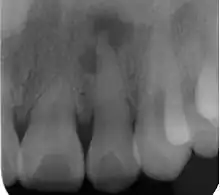

Radiograph (X-ray) showing microdontia. Note also periapical lesion on the maxillary left lateral incisor.

Microdontia is a condition in which one or more teeth appear smaller than normal. In the generalized form, all teeth are involved. In the localized form, only a few teeth are involved. The most common teeth affected are the upper lateral incisors and third molars.

Localized microdontia is also termed focal, or pseudo-microdontia. A single tooth is smaller than normal.[3] Localized microdontia is far more common than generalized microdontia,[2] and is often associated with hypodontia (reduced number of teeth).[1] The most commonly involved tooth in localized microdontia is the maxillary lateral incisor, which may also be shaped like an inverted cone (a "peg lateral").[3] Peg laterals typically occur on both sides,[2] and have short roots.[2] Inheritance may be involved,[2] and the frequency of microdontia in the upper laterals is just under 1%.[1] The second most commonly involved tooth is the maxillary third molars,[3] and after this supernumerary teeth.[3]